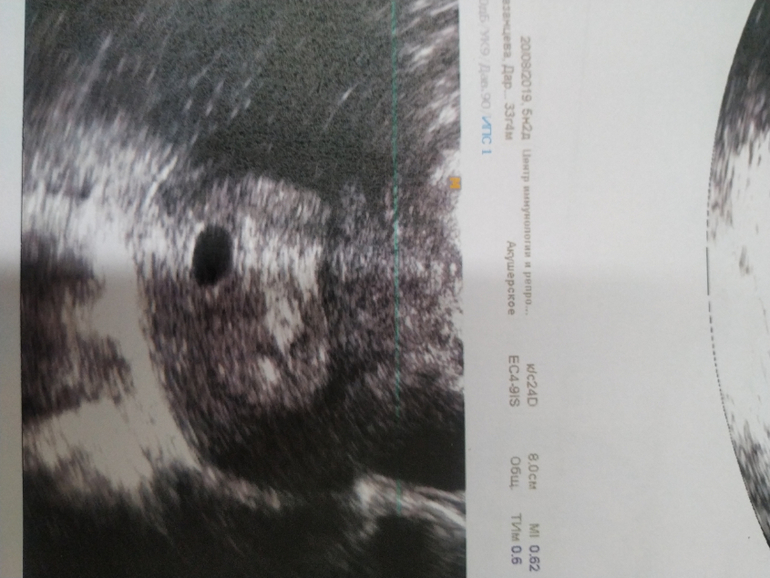

Девочки,подскажите,может ли быть все хорошо? Пошла на узи,врач назначила для подтверждения маточной беременности. Хгч сдаю регулярно,рост нормальный. Сегодня 23 ДПО или 10дз. Это моя первая в жизни и очень долгожданная беременность,очень переживаю. НА узи нашли только плодное яйцо д9мм,про жм и тем более эмбрион ничего не сказали,врач какой-то вялый,я спрашиваю все хорошо,он ну поменьше ,типо маленький срок. спросил про хгч,сказал, ну это нормальный рост. Типо развивающуюся пока поставить не могу,просто беременность малого срока. Приходи мол через 2 недели.(оборудование должно быть хорошее,делала в ЦИРе)

Не было ничего на 5 неделе, фото скинула вам. Только плодное яйцо. Срок маленький ещё не видно ничего. Не надо переживать, это вредно

Это узи на 5 неделе, а следующее уже в 7 недель.